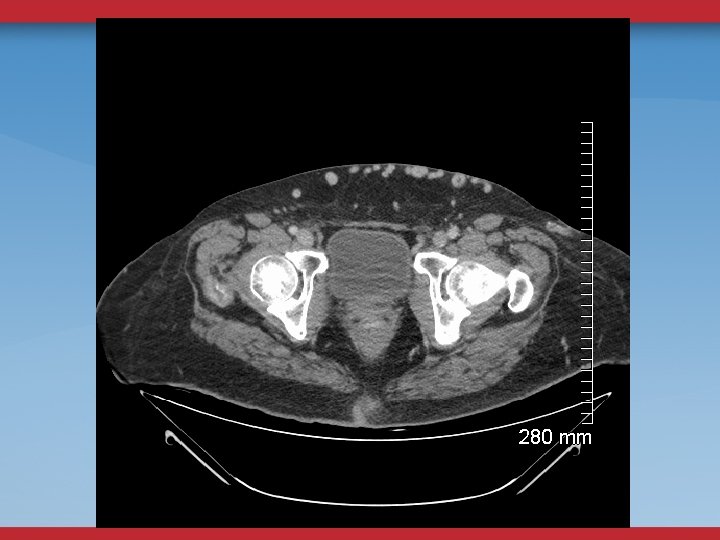

CT/MR VENOGRAMS - HELP WITH ANATOMIC DETAIL - DO NOT EVALUATE FLOW - DEPENDENT UPON FACILITY AND RADIOLOGIST INTEREST - CT— TIMING OF CONTRAST INJECTION/FLOW ISSUES

DEFINITIVE DIAGNOSTIC/THERAPEUTIC PROCEDURES VENOGRAMS UG sheath placement Femoral, Pop, PTV Flow, Collaterals

VENOGRAMS FEMORAL INFLOW FILLING DEFECTS WILL MISS SOME STENOSES, WEBS

INTRAVASCULAR ULTRASOUND THE ANATOMIC GOLD STANDARD USUALLY BILATERAL IFV/IVC CHOOSE DIAMETER/LENGTH OF BALLOON/STENT POST-STENTING ASSESSMENT